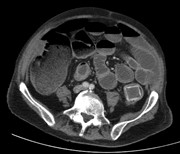

Synchronous tumours of the breast and bladder

David Wallace and others

Journal of Surgical Case Reports, Volume 2014, Issue 7, July 2014, rju066, https://doi.org/10.1093/jscr/rju066